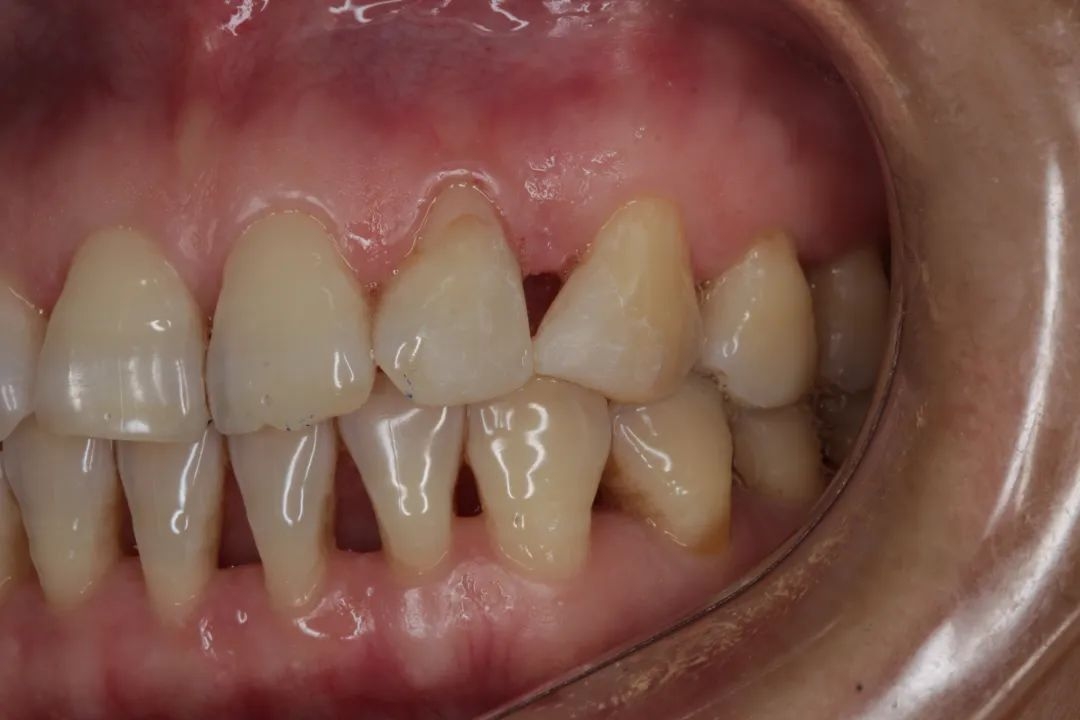

慢慢地,你不在意,牙龈只是有点退缩,然后牙齿缝慢慢显露出来,露出难看的「黑三角」。

由于牙龈退缩,牙齿之间形成了「黑三角」,此时要治疗和改善已经非常困难,图源:作者提供